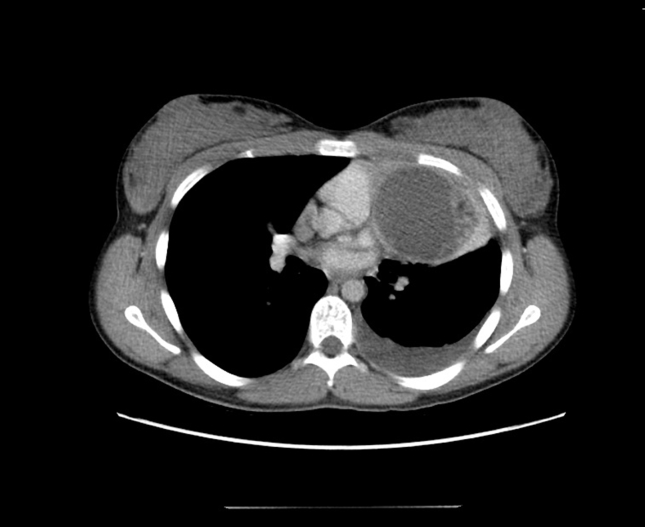

A CT scan of chest and abdomen was arranged. It revealed a 7 cm round, cystic lesion consisting of fat tissue and calcification in the anterior mediastinum, pleural effusion and atelactatic changes in left lung and an enlarged lymph node close to arcus aorta (Fig. 2).

Fig. 2.

A CT scan of chest and abdomen revealing a 7 cm round, cystic lesion consisting of fat tissue and calcification in the anterior mediastinum, pleural effusion and atelactatic changes in left lung, an enlarged lymph node of 1.0 cm close to arcus aorta.